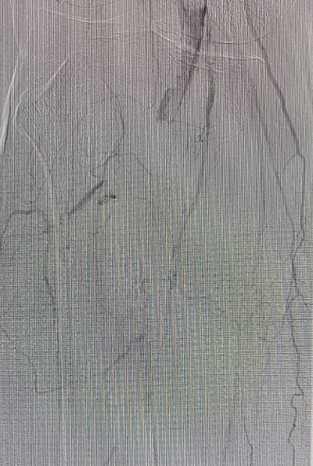

“Artéria poplítea apresentando falhas de enchimento próxima à interlinha articular e oclusão no segmento infragenicular. Artérias tibial anterior, tibial posterior e fibular ocluídas. Arco plantar e arco dorsal ocluídos”.